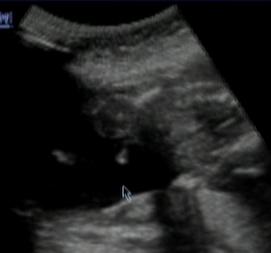

Caute kocky tak my cakame chlapciatko 😵 😵 😵 😵 😵 😵 a veru vianocne ozdoby mu tam visia riadne 😀 😀 😀 😀 😀 som stastna maly bol uzasny zatial je vsetko ok mame 180 az 190g a varu lezal si tam vegetak na bruchu 😅 😵 😵 😵